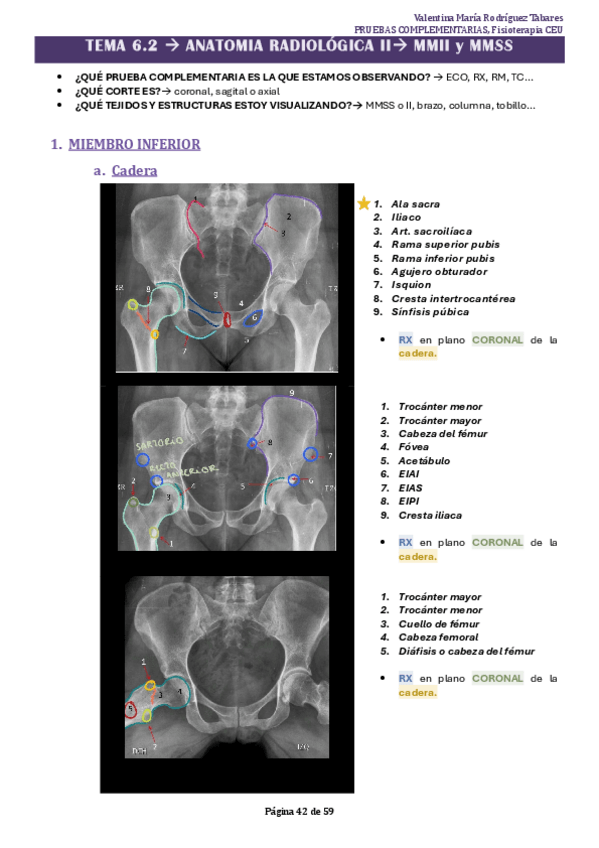

Apuntes - TEMA-6.2-PRUEBAS.pdf

17 páginas

22